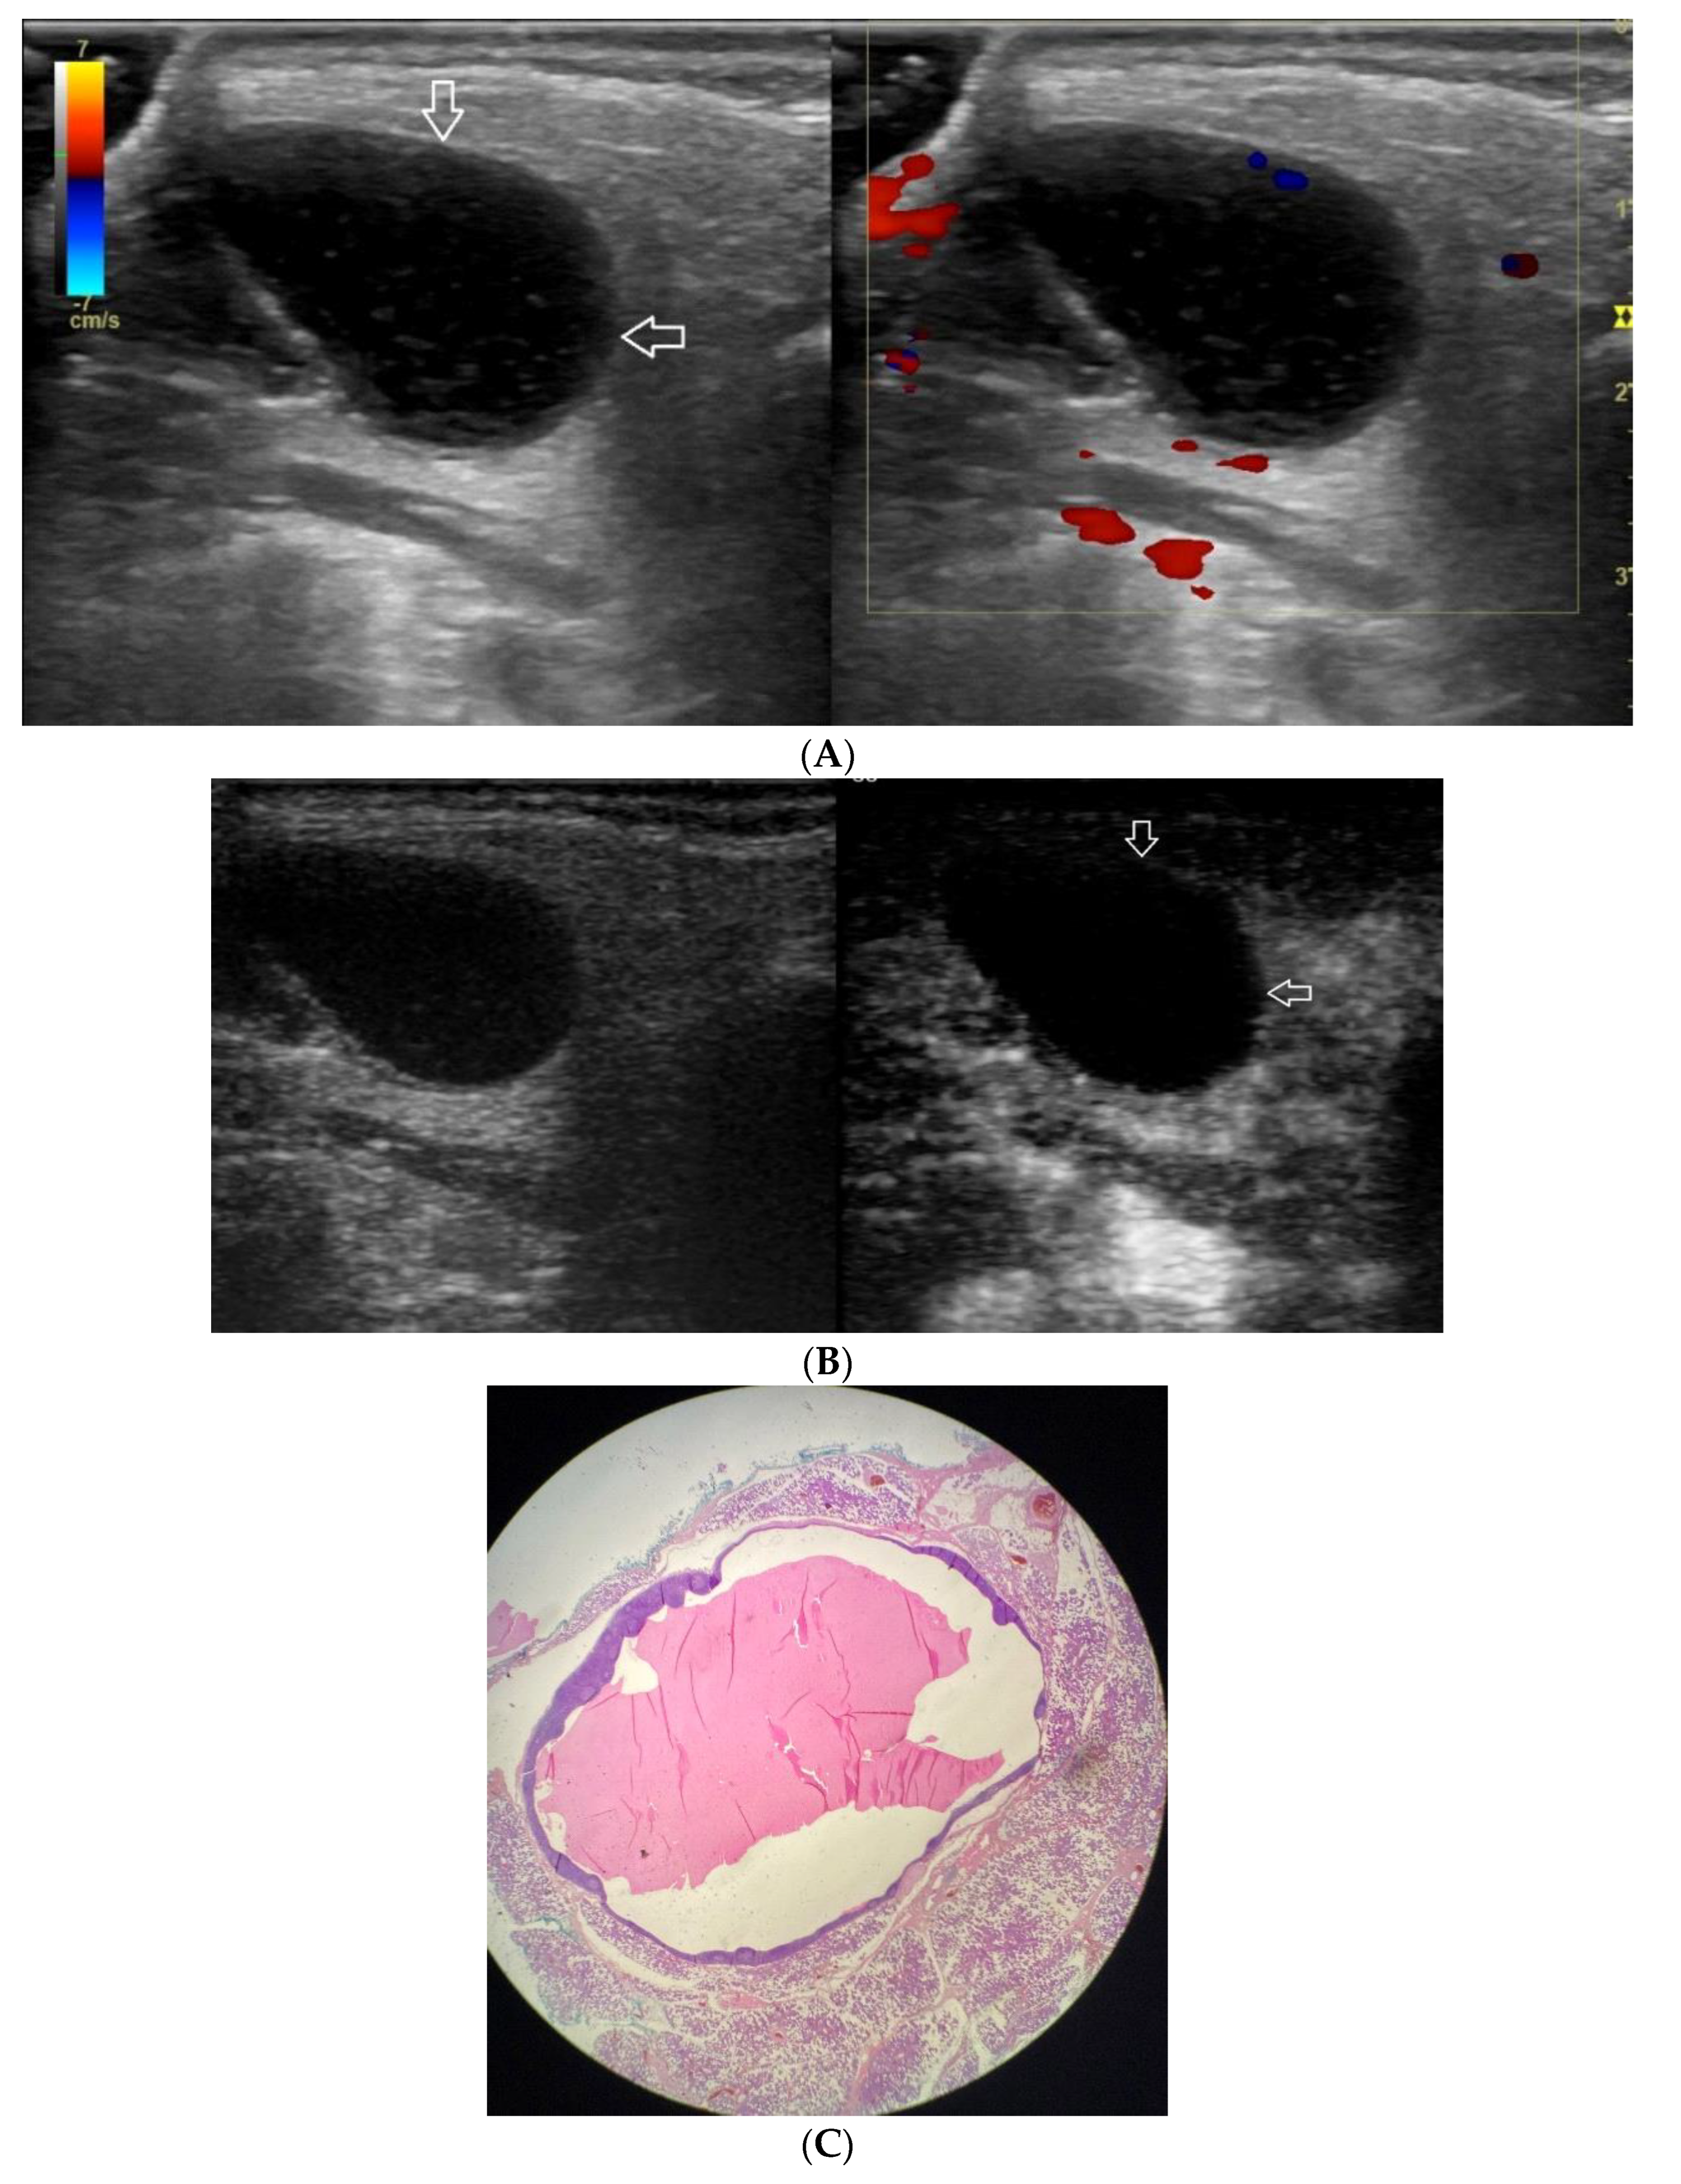

Figure 6.

(A−C) Lymphoepithelial cyst. (A) Routine ultrasonographic examination in B presentation and colour Doppler: an oval hypoechogenic well-demarcated focal lesion of a homogeneous echostructure (white arrows). On CD, no blood flow within the lesion is observed. (B) Contrast-enhanced imaging in arterial phase: no contrast enhancement of the lesion is observed (white arrows). (C) Pathomorphological image, H & E stain. A large area containing fluid with no signs of neoplastic growth.